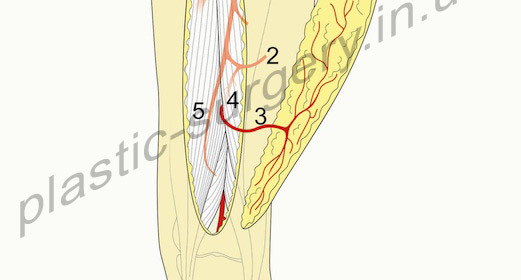

АНАТОМО-ТОПОГРАФИЧЕСКИЕ ОСОБЕННОСТИ И ВЫДЕЛЕНИЕ ЛОСКУТА. В статье представлены варианты заднего кожно-фасциального лоскута бедра, получающего питание от перфорантных артерий и позволяющего восстановить мягкотканный покров в области коленного сустава по всей его окружности. В связи с тем, что перфорантные сосуды, питающие кожу этой области и позволяющие формировать лоскут на их основе, не имеют анатомического постоянства, мы представляем два варианта формирования заднего кожно-фасциального лоскута бедра: на третьем перфоранте глубокой артерии бедра и на перфоранте подколенной артерии (Рис. 1 и 2). Обычно, когда один из этих сосудов является доминирующим, он достаточен для обеспечения питания лоскута. Кровоснабжение данной зоны и самого лоскута было детально описано Тейлором и Палмером (1987) [19].

Задний лоскут бедра на перфоранте подколенной артерии (Popliteal Artery Perforator (PAP-s Flap). PAP-s лоскут впервые был описан как задне-подколенный бедренный кожно-фасциальный лоскут в 1989 году Maruyama и Iwahira [15] для закрытия циркулярного дефекта коленного сустава. Это кожно-перегородочный перфорантный лоскут. В оригинальном его описании в состав лоскута включается фасция, однако это не является обязательным, так как лоскут включает перегородочную перфорантую артерию. Зона кожи, которая может выжить, получая питание от перфоранта подколенной артерии очень схожа с зоной, которая может быть поднята как PFAP – 3 лоскут. PAP-s лоскут может включать в себя кожу от подколенной ямки до подъягодичной складки, по центральной оси задней поверхности бедра (рис. 1).

Рис.1. Схематическое изображение. Задний лоскут бедра на перфоранте подколенной артерии (Popliteal Artery Perforator (PAP-s Flap). (слева) 1- подколенная артерия, 2 – перфорантная артерия, 3- двуглавая мышца бедра, 4- полуперепончатая мышца, 5- полусухожильная мышца (слева).

Рис. 2. Схематическое изображение. Задний лоскут бедра на третьем перфоранте глубокой артерии бедра (Third Perforator of the Profunda Femoris Artery Perforator (PFAP-3) Flap) (справа). 1- глубокая артерия бедра, 2- третий перфорант глубокой артерии бедра, 3- кожный перфорант, 4- двуглавая мышца бедра, 5- полусухожильная мышца (справа).

Сосудистая анатомия. PAP-s лоскут получает питание от ветви подколенной артерии, которая проходит через жировую клетчатку между полуперепончатой и двуглавой мышцей бедра на уровне подколенной ямки. Эта ветвь встречается как основная только в одной трети случаев. Перфорант пронизывает глубокую фасцию бедра на уровне вершины подколенной ямки и разветвляется в коже, на уровне от 2 до 10 см. выше сгибательной складки подколенной ямки. Диаметр основной ветви подколенной артерии колеблется от 1,5 до 2,5 см., она сопровождается веной соответствующего калибра.

Задний лоскут бедра на третьем перфоранте глубокой артерии бедра (Third Perforator of the Profunda Femoris Artery Perforator (PFAP-3) Flap). PFAP-3 лоскут был изначально описан как задний лоскут бедра Song et al. [18], который продемонстрировал его использование в двух клинических случаях. Важно различать этот лоскут от PFAP лоскута (латеральный лоскут бедра). PFAP лоскут базируется на том же сосуде, который дает латеральную ветвь, перфорирующую латеральную межмышечную перегородку. В отличие от этого, PFAP-3 (задний бедренный) лоскут, базируется на задней ветви, которая идет медиально в срединном направлении задней поверхности бедра (рис.2). Задняя ветвь присутствует в 86% случаев. Это самая крупная из всех ветвей отходящих от первого, второго, или третьего перфорантов глубокой артерии бедра, которая следует в срединном направлении бедра. Кожный перфорант, который дает питание PFAP-3 лоскуту локализуется приблизительно на 2/3 расстояния между бугристостью сидалищной кости и средней точкой между мыщелками большеберцовой кости. Эта линия также определяет среднюю ось лоскута. Размеры кожного лоскута могут быть от бедренно-ягодичной складки до нижнего края подколенной ямки. Перфоратор, питающий этот лоскут, выходит в промежутке между двуглавой мышцей бедра и полусухожильной мышцами.

Сосудистая анатомия. Третий перфорант глубокой артерии бедра выходит ниже короткой приводящей мышцы бедра, и ниже сухожилия длинной приводящей мышцы бедра. Этот сосуд проходит кзади через длинную приводящую мышцу и короткую головку двуглавой мышцы бедра, и затем отдает ветви к широкой наружной мышце бедра (vastus lateralis m.). Третий перфорант глубокой артерии бедра в итоге дает ветвь, которая идет вдоль латеральной межмышечной перегородки и питает кожу латеральной поверхности бедра и латеральный лоскут бедра, и задне-латеральные мышцы бедра. Далее эта ветвь кровоснабжает двуглавую мышцу бедра, она также перфорирует глубокую фасцию и питает кожу центральной части задней поверхности бедра и является источником питания для PFAP-3 лоскута. Длина этой сосудистой ножки лоскута колеблятся от 5 см. до 10,7 см. А диаметр этой артерии колеблется от 1,5 до 2 мм. Сопровождающая вена имеет сходный размер.